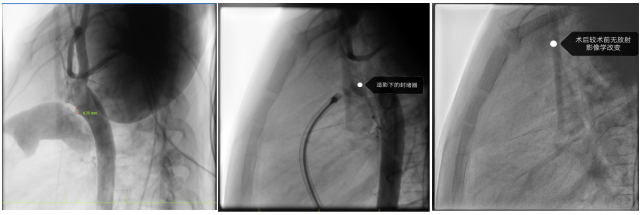

2025年11月7日,玉溪市人民医院心内科团队在广东省人民医院张智伟教授指导下,成功完成云南省首例生物全降解动脉导管未闭(PDA)介入封堵治疗。

患者为4岁男性患儿,体检发现先天性心脏病:动脉导管未闭,分流4.3mm,且左心房已经扩大,来我院就医希望能得到进一步及时诊治。

由于患者年仅4岁,经团队评估后,适合选择介入无金属植入物的全降解封堵器封堵治疗。目前的全降解封堵器由生物高分子材料组成,配合三层阻流膜设计,可有效降低残余分流的风险,且后续无金属植入物在体内,大大减少对未来生活、工作、心理等影响。

在张智伟教授指导下,玉溪市人民医院心内科团队手术过程中,精准定位动脉导管分流位置,将生物可降解封堵器成功植入,实现了对分流的有效封堵。术后超声评估封堵器周围无残余分流,封堵器占位良好。